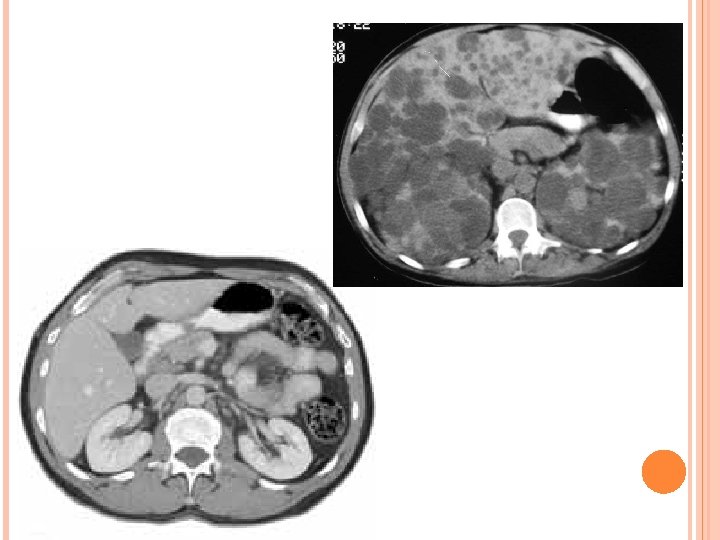

Rein : kystes rénaux – Apparaissent vers 20 ans – Douleurs lombaires et abdominales – hématurie macroscopique et hémorragie intra kystique – Infection urinaire et infection kystique – lithiases urinaires – HTA – IRCT – Cancer du rein

Foie : kystes hépatiques – ¾ patients – Hépatomégalie importante – Pas d’insuffisance hépatique mais Compression, infection de kyste, hypertension portale Rare : kyste pancréas, ovaires, testicules

Diagnostic : – Arbre généalogique – Écho rénale : Inférieur a 30 ans Au moins 2 kystes uni ou bilatéraux 30 – 59 ans Au moins 2 kystes dans chaque rein Supérieur à 60 ans Au moins 4 kystes dans chaque rein – Dépistage des autres atteintes que le rein (écho hépatique, écho cardiaque, coloscopie, angio IRM cérébrale) – Dépistage des cas familiaux